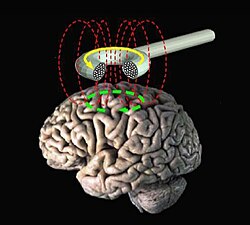

To do this, a doctor or a therapist uses a special machine that produces a magnetic field. This machine has a wand that is placed on the scalp, like a big shiny pencil. The wand sends the magnetic field through the scalp and skull and into the brain, where it activates certain neurons or brain cells. This electrical stimulation helps to improve brain function, such as in cases where someone has depression or anxiety.

To do this, a doctor or a therapist uses a special machine that produces a magnetic field. This machine has a wand that is placed on the scalp, like a big shiny pencil. The wand sends the magnetic field through the scalp and skull and into the brain, where it activates certain neurons or brain cells. This electrical stimulation helps to improve brain function, such as in cases where someone has depression or anxiety.